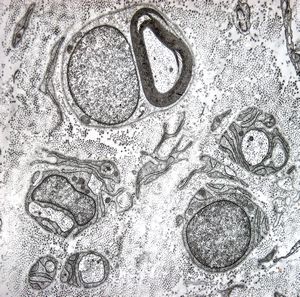

F,23y. | - n.suralis- hypertrophic demyelinizing neuropathy (onion bulbs)